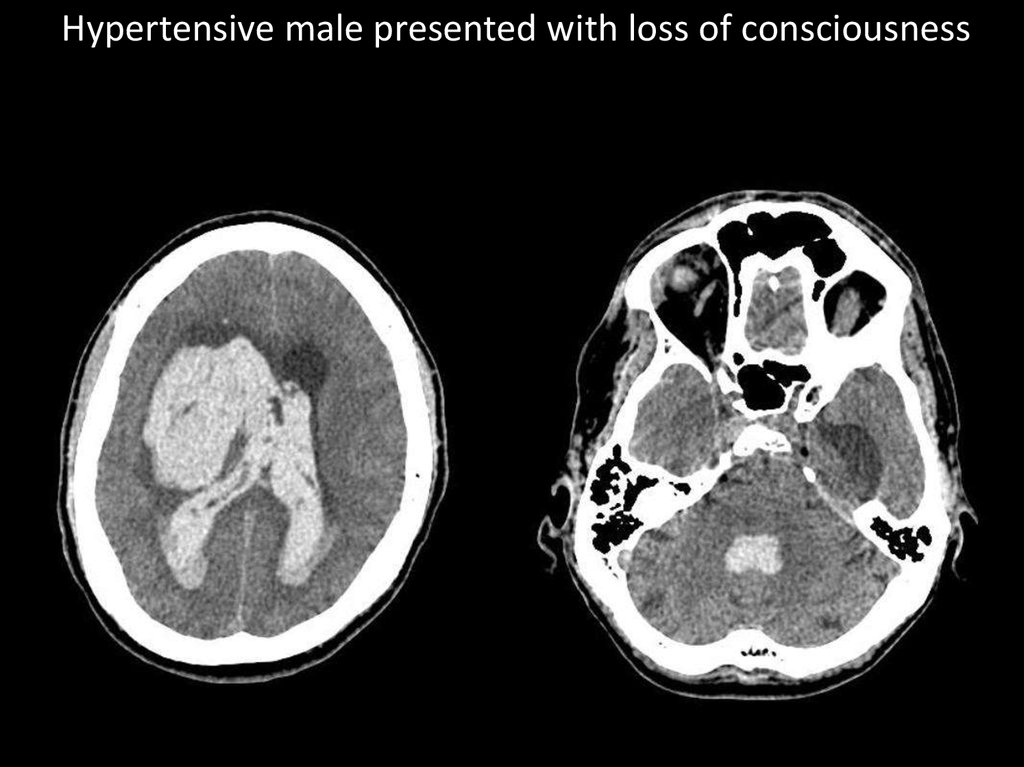

Hypertensive male presented with loss of consciousness

10.